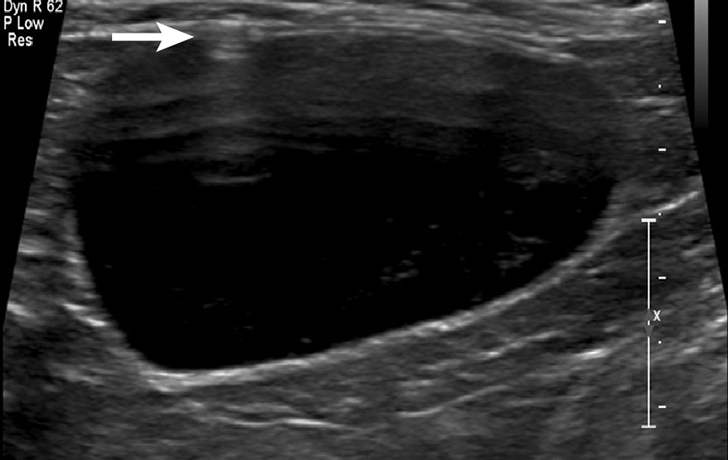

FIGURE 1

Ultrasonographic image showing the cranial aspect of the urinary bladder (A), identified just before ultrasound-guided cystocentesis. It is important to adjust the depth of the image so that the urinary bladder is focused and to consider the depth of the urinary bladder using a machine scale that should be present on the ultrasound screen; in smaller patients the needle may only be partially inserted and not reach the hub (B; arrow).